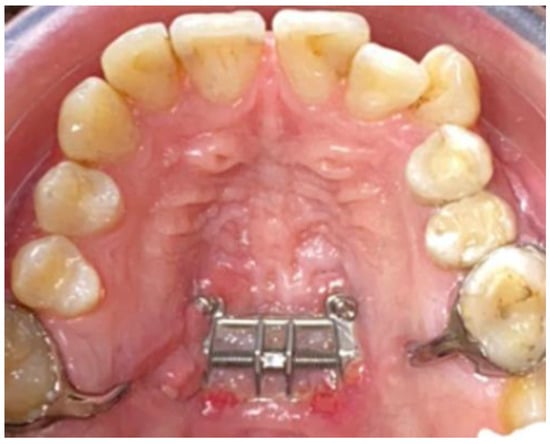

2. Material and Method

2.1. Outcome Measures

2.2. Clinical Outcomes